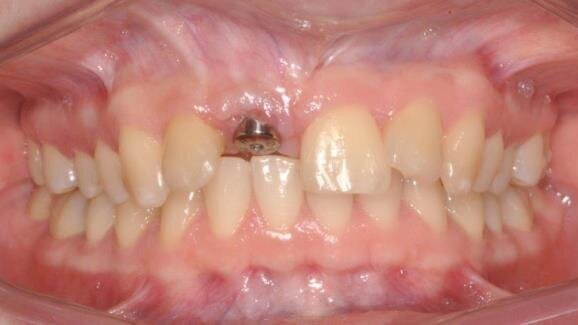

Pacjentka zgłosiła się na kolejną wizytę kontrolną po 3 miesiącach, w miejscu zabiegu tkanki miękkie były wygojone prawidłowo, błona śluzowa dziąsła w okolicy usuniętego zęba była gładka i lśniąca. Śruby do osteosyntezy usunięto po 6 miesiącach po zabiegu (Ryc. 7). Wykonano także kontrolne badanie CBCT, które ujawniło postępujący proces integracji wszczepionego materiału allogennego z otaczającą tkanką kostną. W czasie zabiegu usunięcia śrub mocujących widoczny przeszczep był zintegrowany z kością i dobrze ukrwiony. W miejsce braku zęba 11, po okresie 6 miesięcy od zabiegu sterowanej regeneracji kości, wprowadzono implant stożkowy GS III 3,5 x 13 mm, firmy Osstem (Ryc. 8). Po 6-miesięcznym okresie wgajania odsłonięto implant prawidłowo zintegrowany z kością i przykręcono łącznik gojący (Ryc. 9). Po 3 tygodniach uzyskano zadowalający profil wyłaniania implantu. (Ryc. 10). Wykonano odbudowę protetyczną w postaci korony porcelanowej cementowanej na implancie (Ryc. 11). W trakcie badania stabilności implantu urządzeniem Periotest uzyskano uśredniony z 3 pomiarów wynik 3PTV, który potwierdza prawidłową integrację wszczepu z kością. Kolejna wizyta kontrolna miała miejsce po 9 miesiącach (Ryc. 12).